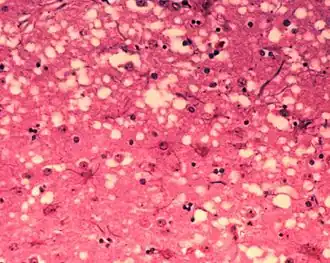

Weefsels die getroffen zijn door prionen vertonen een karakteristieke sponsachtige structuur